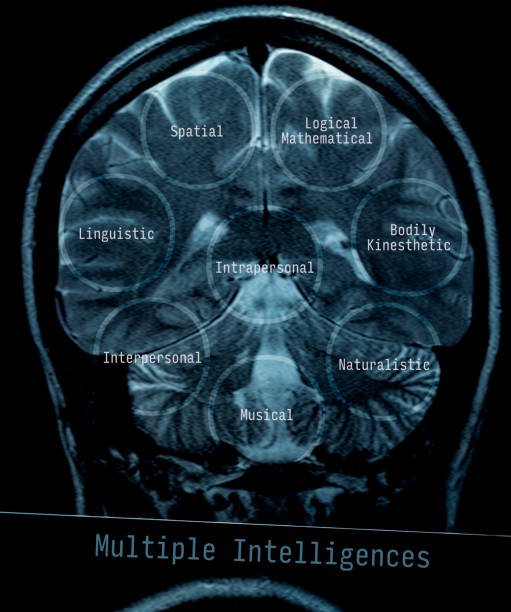

3. MRI (Magnetic Resonance Imaging)

- How it works: MRI uses strong magnetic fields and radio waves to create detailed images of the brain.

- Why it’s useful: It can detect smaller bleeds and provide more detailed images than a CT scan in certain cases.